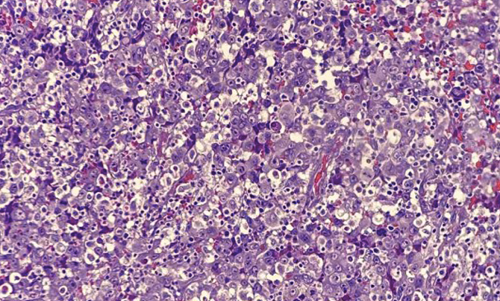

A Case Report on Carcinosarcoma of the Pancreas with a Concise Literature Review

Christine Santos, Rosalie Sabina Michiko Samonte

57-64

PDF